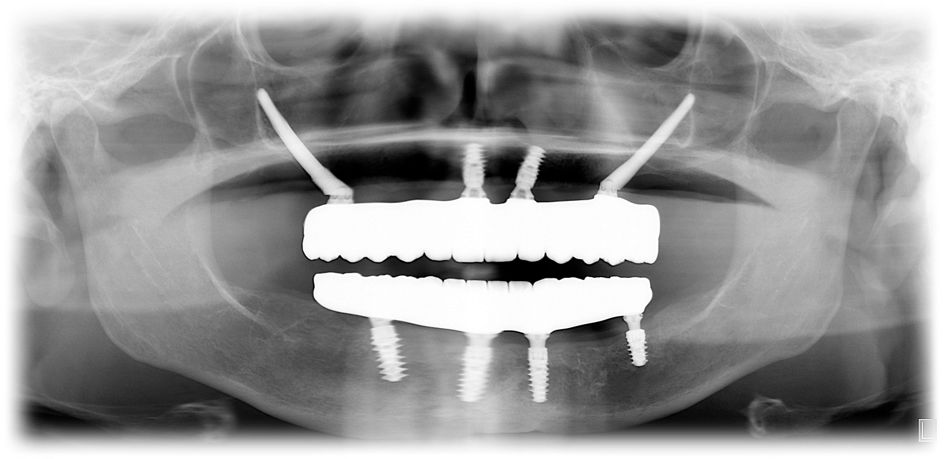

A panoramic radiograph was taken to monitor the health around a dental implant at prosthesis delivery (Fig. 15).